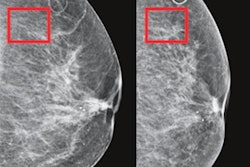

Under the research agreement, a dataset of breast biopsy slides will be included, which will then be digitized using a digital pathology scanner and then analyzed for cancer detection by Ibex's Galen Breast software. Independently, multiple pathologists from Institut Curie will diagnose the slides, followed by blinded analysis of Galen Breast's performance.

The AI software was developed using machine learning and trained on hundreds of thousands of image samples, Ibex Medical Analytics said. The software is already in use at the pathology institute of Maccabi Healthcare Services, Israel's second-largest HMO, where it is used as a second-read.